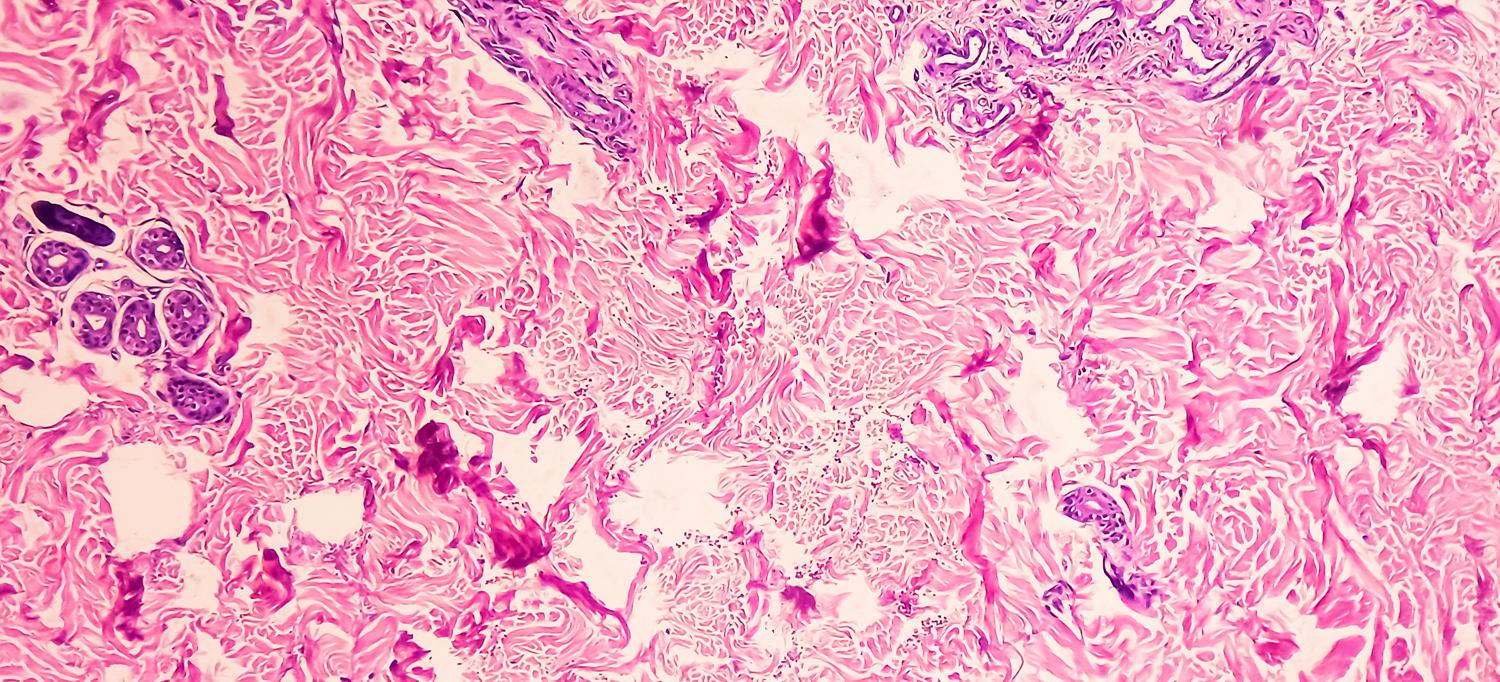

Credit: Getty/Md Babul Hosen